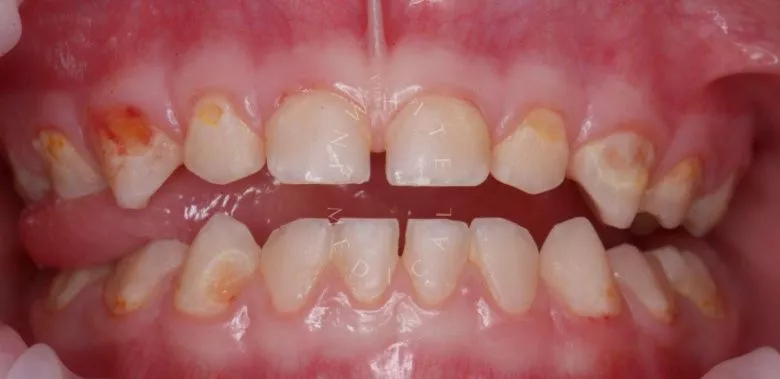

Лечение под наркозом - установка коронок и профессиональная гигиена у детей

етская стоматология лечение под наркозом. Лечение под наркозом - установка коронок и профессиональная гигиена у детей - до процедуры

етская стоматология лечение под наркозом. Лечение под наркозом - установка коронок и профессиональная гигиена у детей - после процедуры